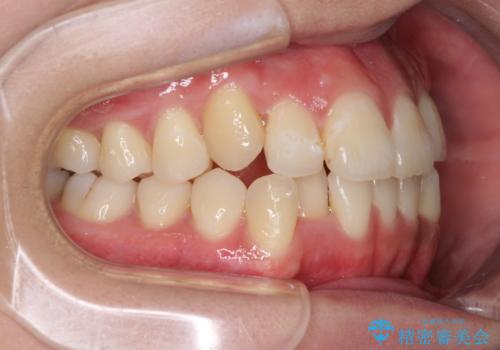

- 前歯のデコボコと残っている乳歯の部分へのインプラント治療を希望して来院された患者様です。

当初は目立たない上下裏側矯正を希望されていましたが、歯並びの悪さによる磨き残しが多く、歯肉炎が認められたため、より清潔な環境で治療を進められるインビザラインを選択することとしました。

前歯のデコボコが強かったため、上の奥歯を後方に動かす量が多くなり、結果として2年以上の治療期間を擁することとなりました。